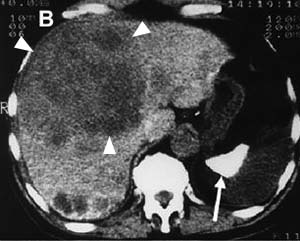

図6. 69歳男性.49年前,上肢骨折に対してトロトラストにて血管造影を施行,急性腹症にて発症.大きな低吸収の腫瘍があり(▲),その周囲にはトロトラスト沈着による網目状の高吸収が認められる.病理診断は血管肉腫. 脾の高吸収,高度萎縮(→)も認められる[9].

トロトラストの障害が初めて正式に報告されたのは,使用開始から約20年後の1947年のことである.肝梅毒腫(ゴム腫)診断目的のトロトラストによる血管造影後,12年を経て発症した肝内皮細胞肉腫の剖検例をMacMahornらが報告し,その因果関係を指摘した[→原著論文].その後も肝腫瘍,再生不良性貧血,白血病などの報告が相次ぎ,各国とも1950年代後半には次第に使用されなくなったが,1964年までに世界各国で10万人以上がトロトラストを投与された.その後の追跡結果は各国で報告されているが,例えばドイツの報告では1969~91年のフォロー期間中,トロトラストを投与された899例中410例に肝腫瘍が発生し,これに対して他の造影剤による検査を受けた対照群662例からの肝腫瘍は2例であった[8].日本の厚生省(当時)による調査でも,1966年までに124例のトロトラスト関連腫瘍が報告されている(肝肉腫が最多,潜伏期平均19.4年)[14,15].腫瘍発生までの潜伏期は16~45年とされるが,これに起因する腫瘍の発生は現在もなお続いている[9,10](図6).

トロトラストは70%が肝に集積し,誘発性腫瘍も肝に最も多い.特に胆管細胞癌,血管肉腫が特徴的であるが,肝細胞癌も発生する.トロトラストはKuppfer細胞に取り込まれて門脈域に主に集積する.ここから放出されるα線の飛程は短いが,沈着巣から範囲10μ近傍の被曝量は100Gy/年にもなり[11],門脈域周囲の細胞が特に障害されて胆管細胞癌,血管肉腫が多くなるものと考えられる.この他にも,胆嚢,肝外胆管,その他全身の悪性腫瘍の増加が知られている[12] .